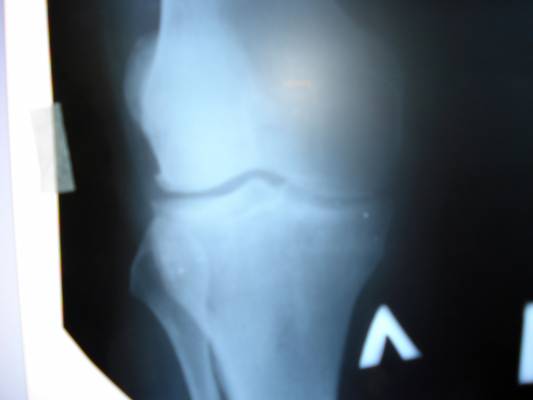

Альбом АРТРОЗ КОЛЕННЫХ СУСТАВОВ. Фото "АРТРОЗ КОЛЕННЫХ СУСТАВОВ" 365.8 k (3072x2304) DSC07566.JPG

АРТРОЗ КОЛЕННЫХ СУСТАВОВ

АРТРОЗ КОЛЕННЫХ СУСТАВОВ 2-3 СТ.???